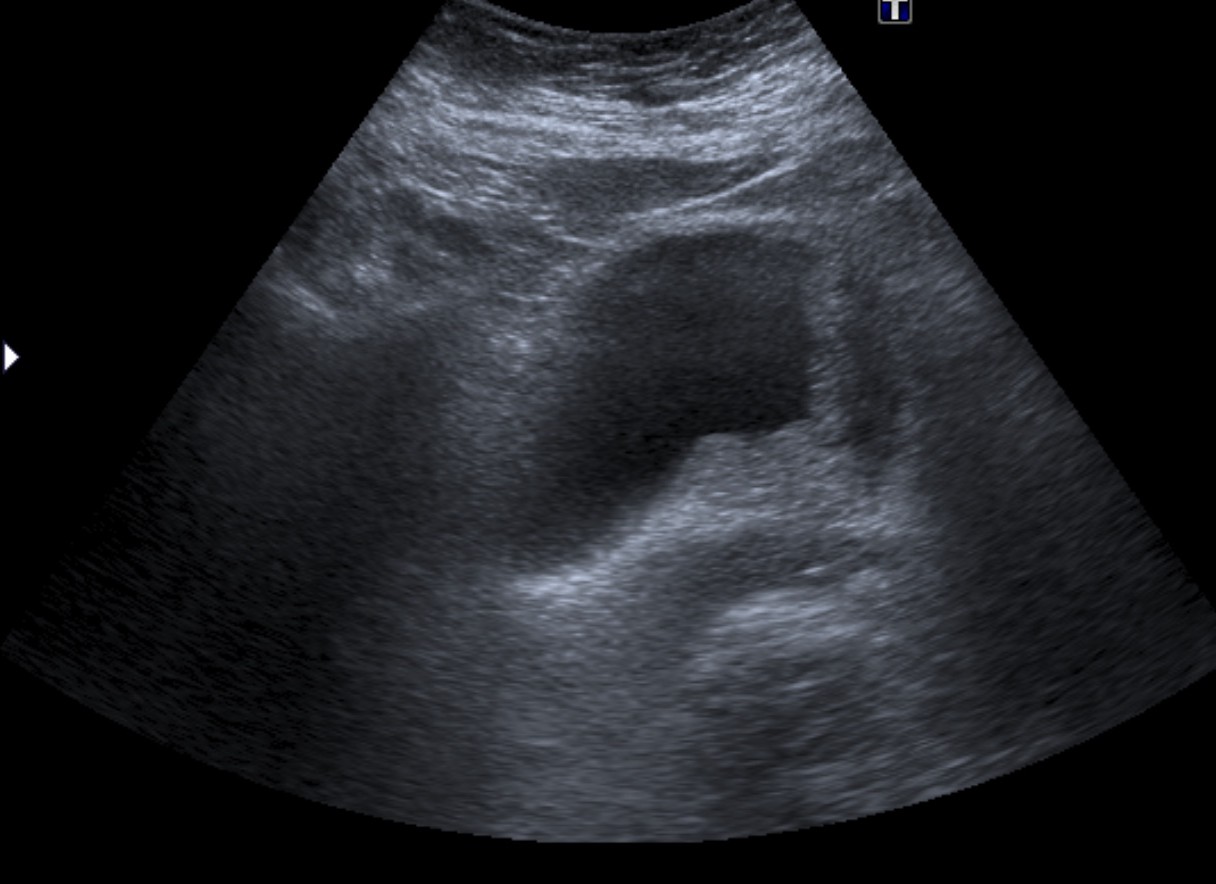

- Ecografía: es una herramienta accesible y se puede usar para una primera valoración de la hematuria. Sin embargo, tiene una sensibilidad del 80% y es poco útil para el diagnóstico de tumores del tracto superior.

Tras el tratamiento de la recidiva y nefrostomía para la hidroureteronefrosis, vuelve acudir al hospital a los 9 meses por episodio de dolor en FD y malestar general. Se realiza una ecografía de urgencias.